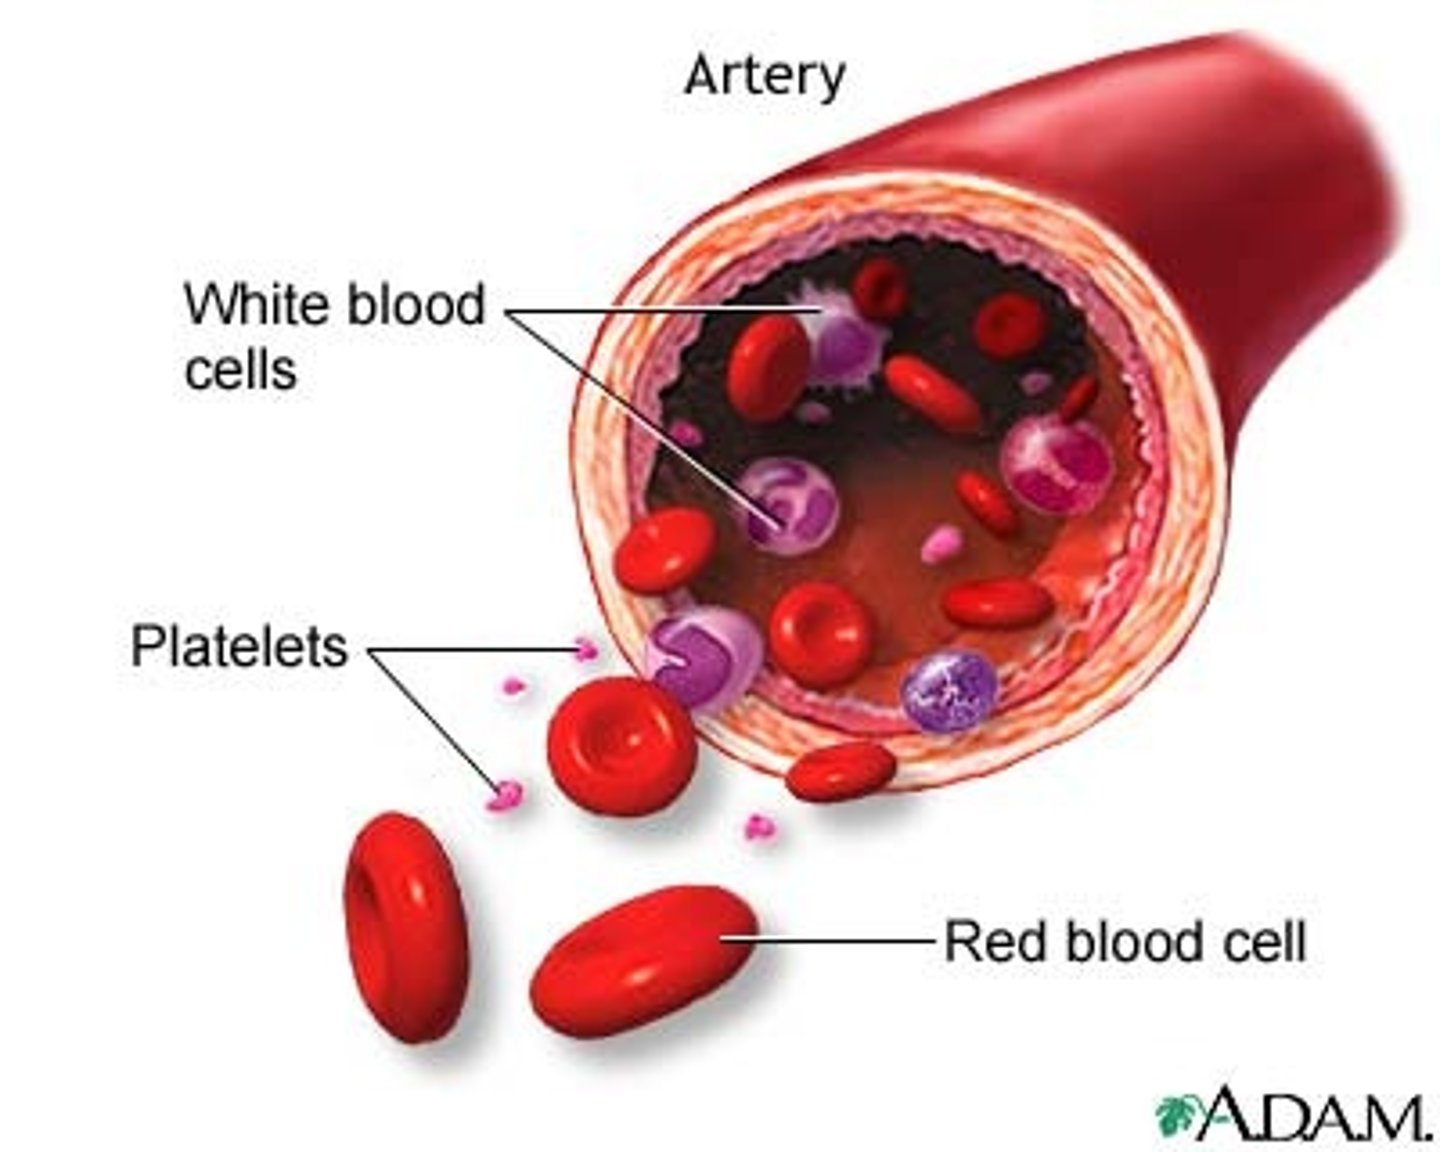

What is the cellular component of blood?

Erythrocytes, leukocytes, thrombocytes (45% of blood)

Leukocytes

White blood cells

Neutrophils

Function: The most common WBC; fights bacterial infections by engulfing bacteria by phagocytosis

Monocytes

Function: A large WBC that transform into macrophages to fight off viruses and chronic infections

Lymphocytes

Function: B cells make antibodies, T cells fight off viral infections, NK cells